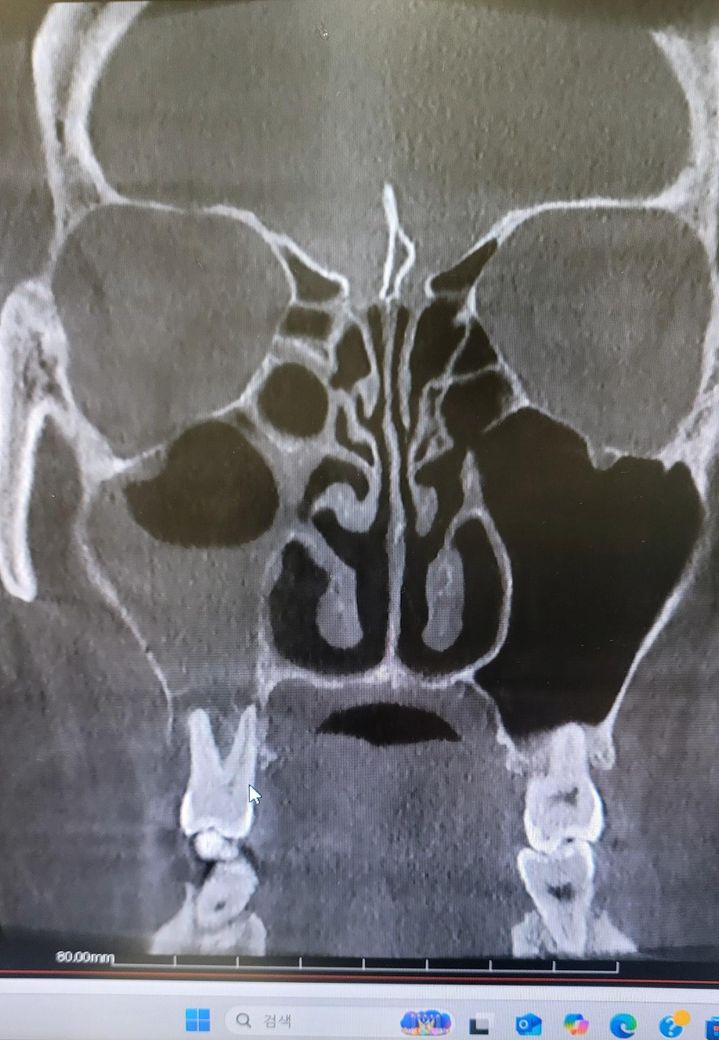

CT를 보시더니 한쪽에 부비동염 농이 차있는데 이로인해 두통이 오는거였고 이게 원인이 치성 부비동염 같다면서

• 1번 째 사진

치아떄문에 생긴 상악동 염증이라면 발치를 하시고 나서 상악동의 염증도 같이 제거를 하시는게 좋을것같습니다. 이미 잇몸뼈가 많이 소실된 상태 같습니다.

사진으로 봤을 경우 치아 주변의 치조골이 이미 손실된것으로 보입니다.

2. 상악동 염증이 꽤 크네요. 이게 치성원인이라면 발치는 불가피하고 발치 후 상악동 세척술 필요합니다.

3. 이미 치아와 상악동 부위는 개통되었을 것 같네요. 발치 후 천공이 문제가 아닙니다.